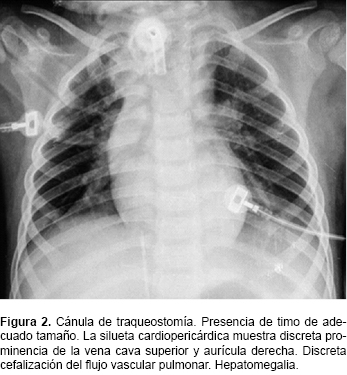

Nina Con Sindrome De Down E Hipertension Pulmonar - En medicina, estenosis o estegnosis (del gr.